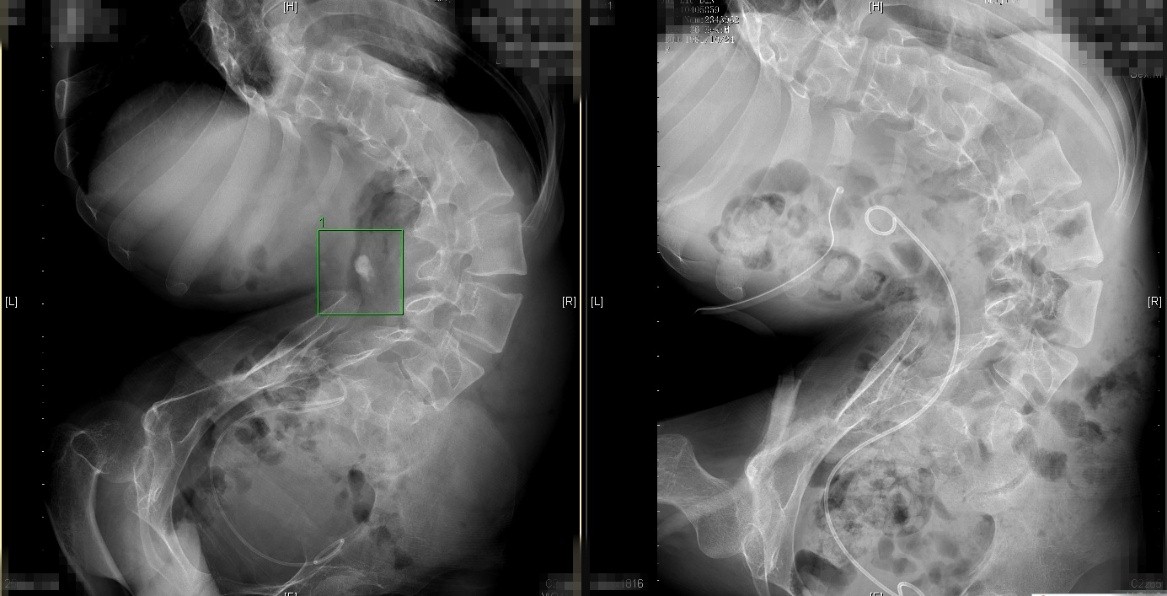

图为小彬术前、术后CT对比影像,绿框内白色亮区为结石

“身体畸形的人,内脏受压变形,尤其对于泌尿系统来说,会造成肾脏移位,输尿管严重迂曲、变异,会比正常人更易患泌尿系结石。”李建兴说,而这一特殊解剖结构也为手术带来了更大的挑战,对医师的手术经验和操作手法提出超高的要求。“身体畸形的患者,手术路径与正常人不同,需要采取非常规区域穿刺,且畸形结构导致穿刺空间狭小,碎石过程也受到了严重限制。用常规的X射线引导定位结石部位无法完成手术,必须使用超声定位。”